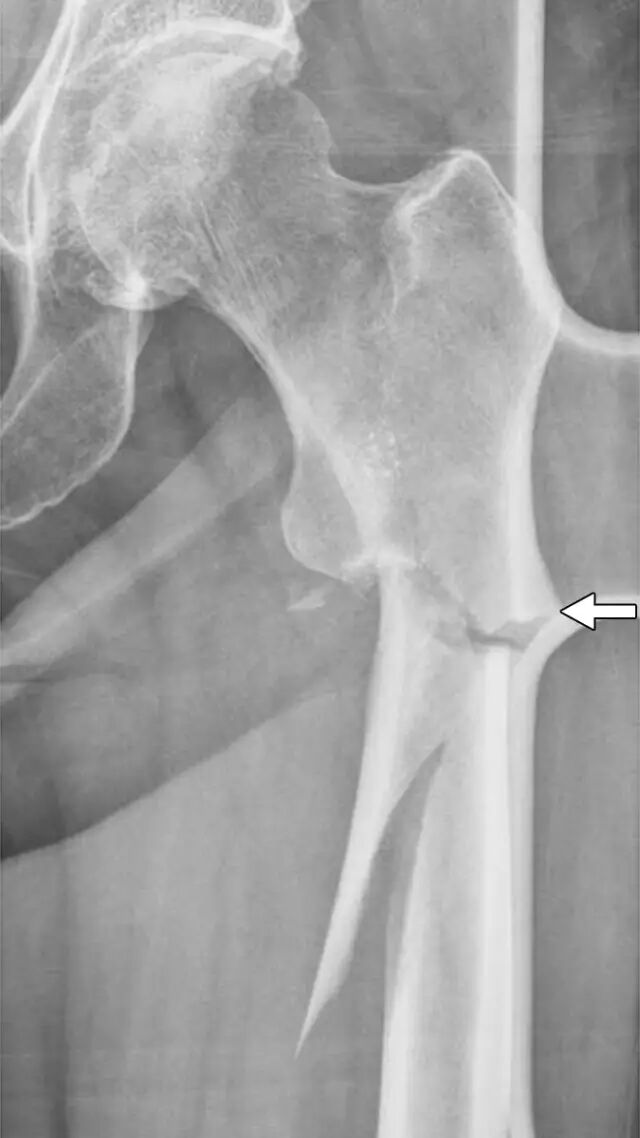

一旦确定了骨折,放射科医生应对其进行表征,以便进一步管理。然而,可能存在放射科医师可以提供超出简单骨折描述的范围的更多信息。特定解剖部位的骨折在特定年龄通常更频繁,并且通常作为特定机制的结果而发生。识别对于部位,年龄和机制不典型的骨折应导致进一步调查。例如,由于大的创伤性事件(例如机动车辆撞击或从高处坠落),近侧股骨轴(转子间或转子间 - 转子间)的骨折通常发生在健康成年人中。近端股骨干骨折可能由于在具有骨骼脆性的非常老年人群中或在具有使骨骨折的某些潜在病症的群体中的地面下降而发生。因此,由于地面跌倒导致的年轻或中年成年人的股骨近端骨折的发现应该引起立即怀疑潜在的预处置状况。经常有关于初始创伤X光片的潜在病理生理学的线索。外侧股骨皮质的增厚,特别是如果存在三角形峰的外观,已被认为是二膦酸相关的不全性骨折的特征[41](图10)局部的骨质破坏可以指示肿瘤或骨髓炎的存在。近端股骨是骨转移的最常见部位[42]。特别是,成年人的小转子股骨骨折的存在应引起强烈的临床关注,由于转移性疾病的病理性骨折[43,44]。该信息对于临床医生在手术治疗中是有价值的。

图10A、B - 两个异常骨折患者。A,65岁的妇女在商场后地面跌倒到急诊部。正位放射照片显示粉碎的股骨粗隆间骨折。她已经服用阿仑膦酸(Fosamax,Merck)10年的骨质疏松症。近端外侧股骨皮质(箭头)的异常增厚部分被创伤板遮蔽。B,46岁的男子在地面跌倒。前后放射照片显示股骨转子间股骨近端骨折与单独的小转子片段和明显的角度。在髓内丁放置时的病理学显示转移性癌症。